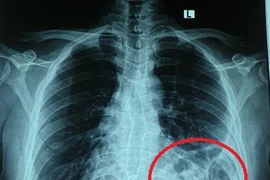

Ho, khó thở tưởng hậu Covid-19, nam thanh niên 25 tuổi cố chịu đựng điều trị tại nhà. Khi ho và tức ngực không chịu được bệnh nhân mới đi khám mới hay thoát vị hoành trái do vỡ cơ hoành.